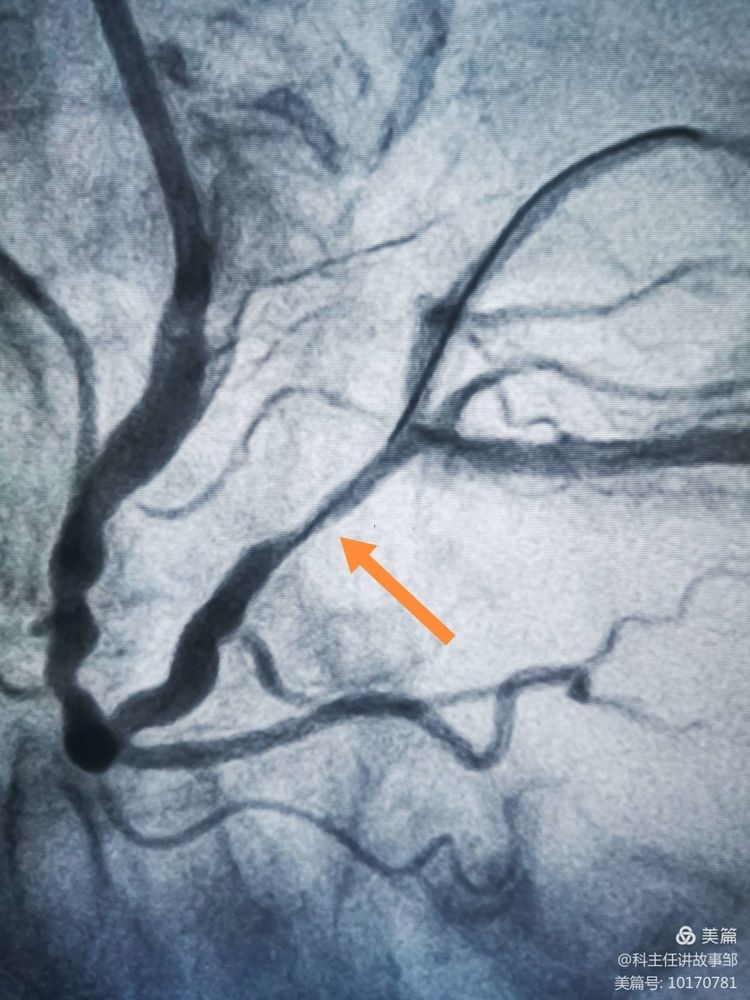

患者胸痛14小時。心電圖提示急性下壁心梗。

造影發(fā)現(xiàn)重度狹窄,接近閉塞。怎么辦?

沒有植入支架。

急性心梗最主要的治療是盡快高效持續(xù)保持血流通暢。不適合支架的時候單純球囊擴張也是一種折衷的辦法,但再狹窄閉塞風(fēng)險要大一些。年齡不是禁忌。